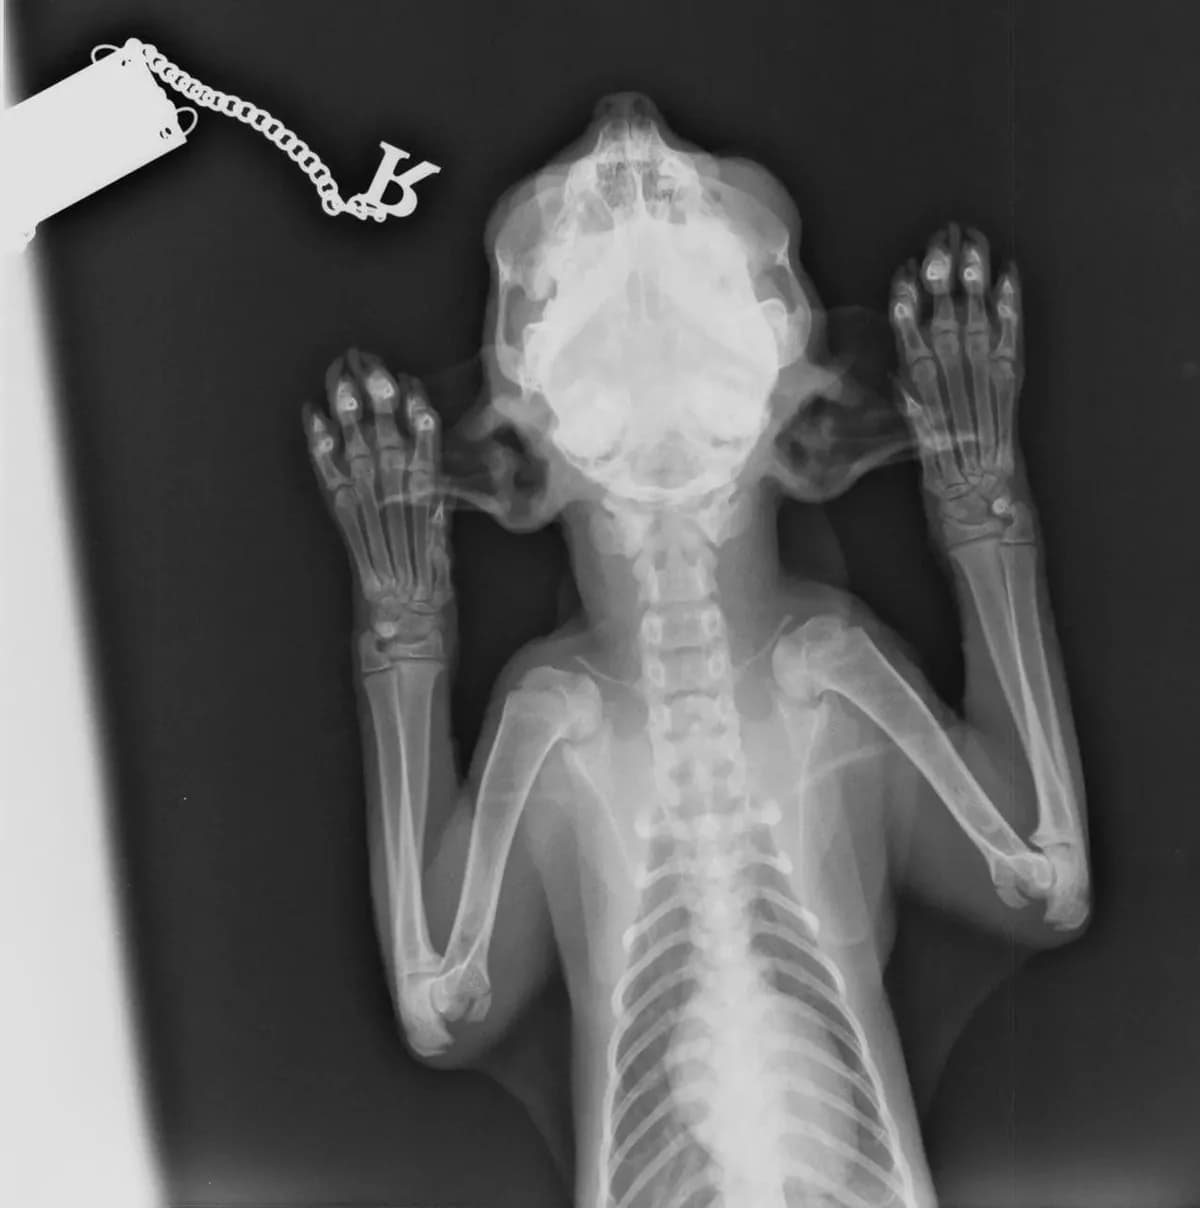

Anfang Mai 2025 wurde Jamiro von unseren griechischen Tierschutzfreundinnen H. & I. auf Andros in einem schlimmen Zustand eingefangen. Er konnte seine Kiefer nicht bewegen und daher auch nicht richtig fressen. At the beginning of May 2025, Jamiro was captured in a terrible condition on Andros by our Greek animal welfare friends H. & I. He couldn't move his jaws and therefore couldn't eat properly. Da die diagnostischen und medizinischen Möglichkeiten für solche Fälle auf Andros nicht gegeben sind, sandten sie den Kleinen nach Rücksprache mit uns zu einer Tierärztin nach Athen, mit der wir bei komplizierteren Behandlungen zusammenarbeiten. Sie röntgte ihn und stellte eine Deformation fest, die Jamiro daran hindert, seine Kiefer zu öffnen und zu fressen. Since the diagnostic and medical resources for such cases are lacking on Andros, after consulting with us, they sent the little one to a veterinarian in Athens with whom we work together for more complex treatments. She x-rayed him and discovered a deformity that prevents Jamiro from opening his jaws and eating. Wir suchten gemeinsam nach einem Spezialisten für Kieferchirurgie und fanden aufgrund eines Hinweises einer Bekannten in Athen jemanden, der sich des Falls annahm. Dieser Spezialist hat natürlich eine entsprechende Praxisausstattung und untersuchte Jamiro gründlich. Together, we searched for a specialist in oral surgery and, thanks to a tip from a friend in Athens, found someone who took on the case. This specialist, of course, has the appropriate equipment and examined Jamiro thoroughly. Er teilte uns mit, dass Jamiro einen alten Bruch im Kiefergelenk hat und beide Gelenke blockiert sind. Er meint, dass die Katze eine einseitige Gnathektomie benötigt, also eine operative Entfernung eines Teils des Kiefers. Er denkt, dass dies ausreicht und dass eine beidseitige Gnathektomie nicht notwendig sein wird. Die Prognose bei einer solchen Operationen ist sehr gut, Jamiro wird wieder normal und sch